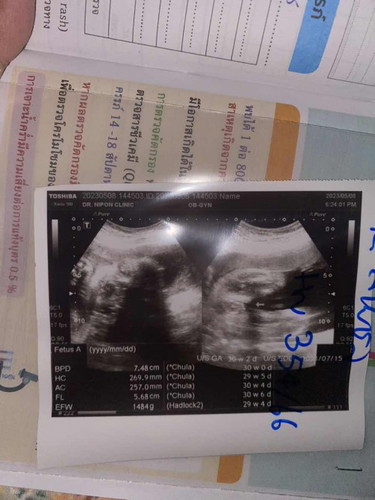

แม่ๆค่ะ29+4วีค น้ำหนักน้อง1484g น้ำหนักน้องน้อยไปรึป่าวค่ะ

เยอะกว่าของเราอีกค่ะ อายุครรภ์เท่ากันเลย29+4 เราก็พึ่งไปหาหมอวันนี้ นน. น้อง1335 แต่แม่โดนกลืนน้ำตาลก่อนไปหาหมอรอบหน้า วันที่26 นัดตรวจเบาหวานอีกเพราะหมอบอกว่าแม่ตัวเล็กน้ำหนักก็ขึ้นไม่เยอะ แล้วซาว4มิติมาเมื่อกี้ คุณหมอว่าแก้มน้องเยอะมาก ตัวก็ตัวน้องออกอ้วนนิดๆๆ